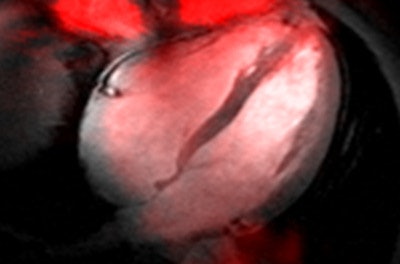

One exciting development that is in the spotlight of current (pre)clinical research is that cutting-edge MR centers are exploiting UHF-MR not only for H-1 MRI but also for documenting the value of 7-tesla MRI for imaging x-nuclei such as carbon (C-13), oxygen (O-17), fluorine (F-19), sodium (Na-23), phosphorous (P-31), chlorine (Cl-35), and potassium (K-39). UHF-MR holds the promise to facilitate sodium imaging of the heart (see figure) with a spatial resolution commonly used for H-1 MR in today's clinical practice at lower fields.1